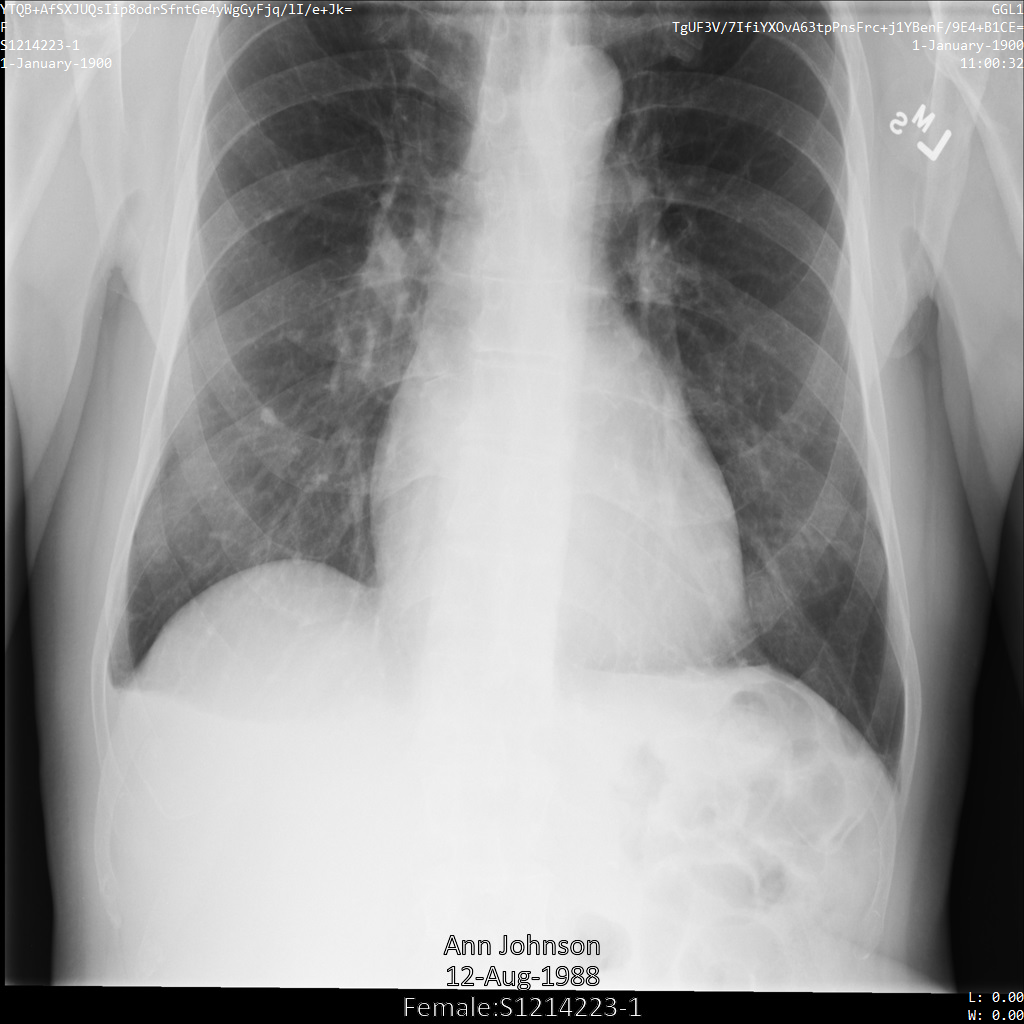

Chacune des sections suivantes fournit des exemples d'anonymisation de données DICOM à l'aide de différentes méthodes. Une sortie de l'image anonymisée est fournie avec chaque échantillon. Chaque exemple utilise l'image d'origine suivante comme entrée :

xray_original

Vous pouvez comparer l'image de sortie de chaque opération d'anonymisation à cette image d'origine pour voir les effets de l'opération.

Une fois l'image envoyée à l'API Cloud Healthcare, elle apparaît comme suit. Alors que les métadonnées affichées dans les angles supérieurs de l'image ont été masquées, les informations de santé protégées qui sont incluses dans l'angle inférieur de l'image sont conservées. Pour supprimer également le texte incrusté, consultez la section Masquer le texte incrusté dans les images.

dicom_keeplist